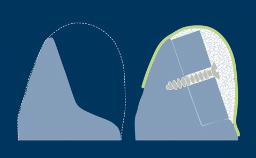

In the case of implant impressions, a precision-made impression component is used to register the position, alignment, and rotational orientation of the implant.

The impression, whether it follows a conventional (that is, analog) or digital workflow, then records this information in relation to the surrounding hard and soft tissues. This module will deal with conventional impression techniques and all of the parameters involved.